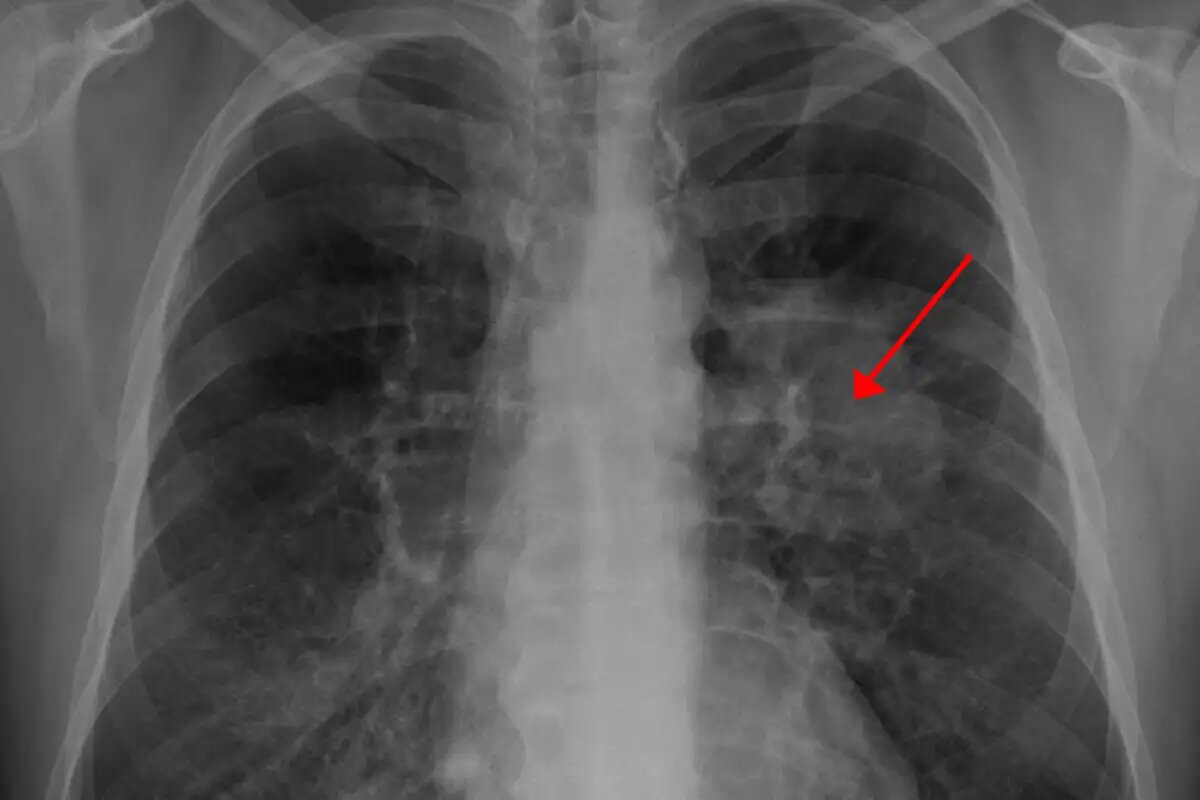

Рентгенограмма грудной клетки, демонстрирующая опухоль в лёгких. © ru.wikipedia.org